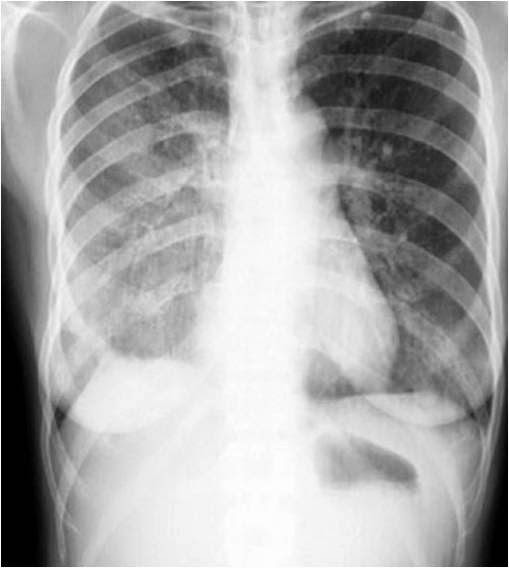

Achalasia cardia

Inlet to Outlet Shadow

Inhomogeneous cardiac density: Right half more dense than left

Density crossing midline (right black arrow)

Right sided inlet to outlet shadow

Right para spinal line (left black arrow)

Barium swallow below: Dilated esophagus

This is a case of achalasia cardi